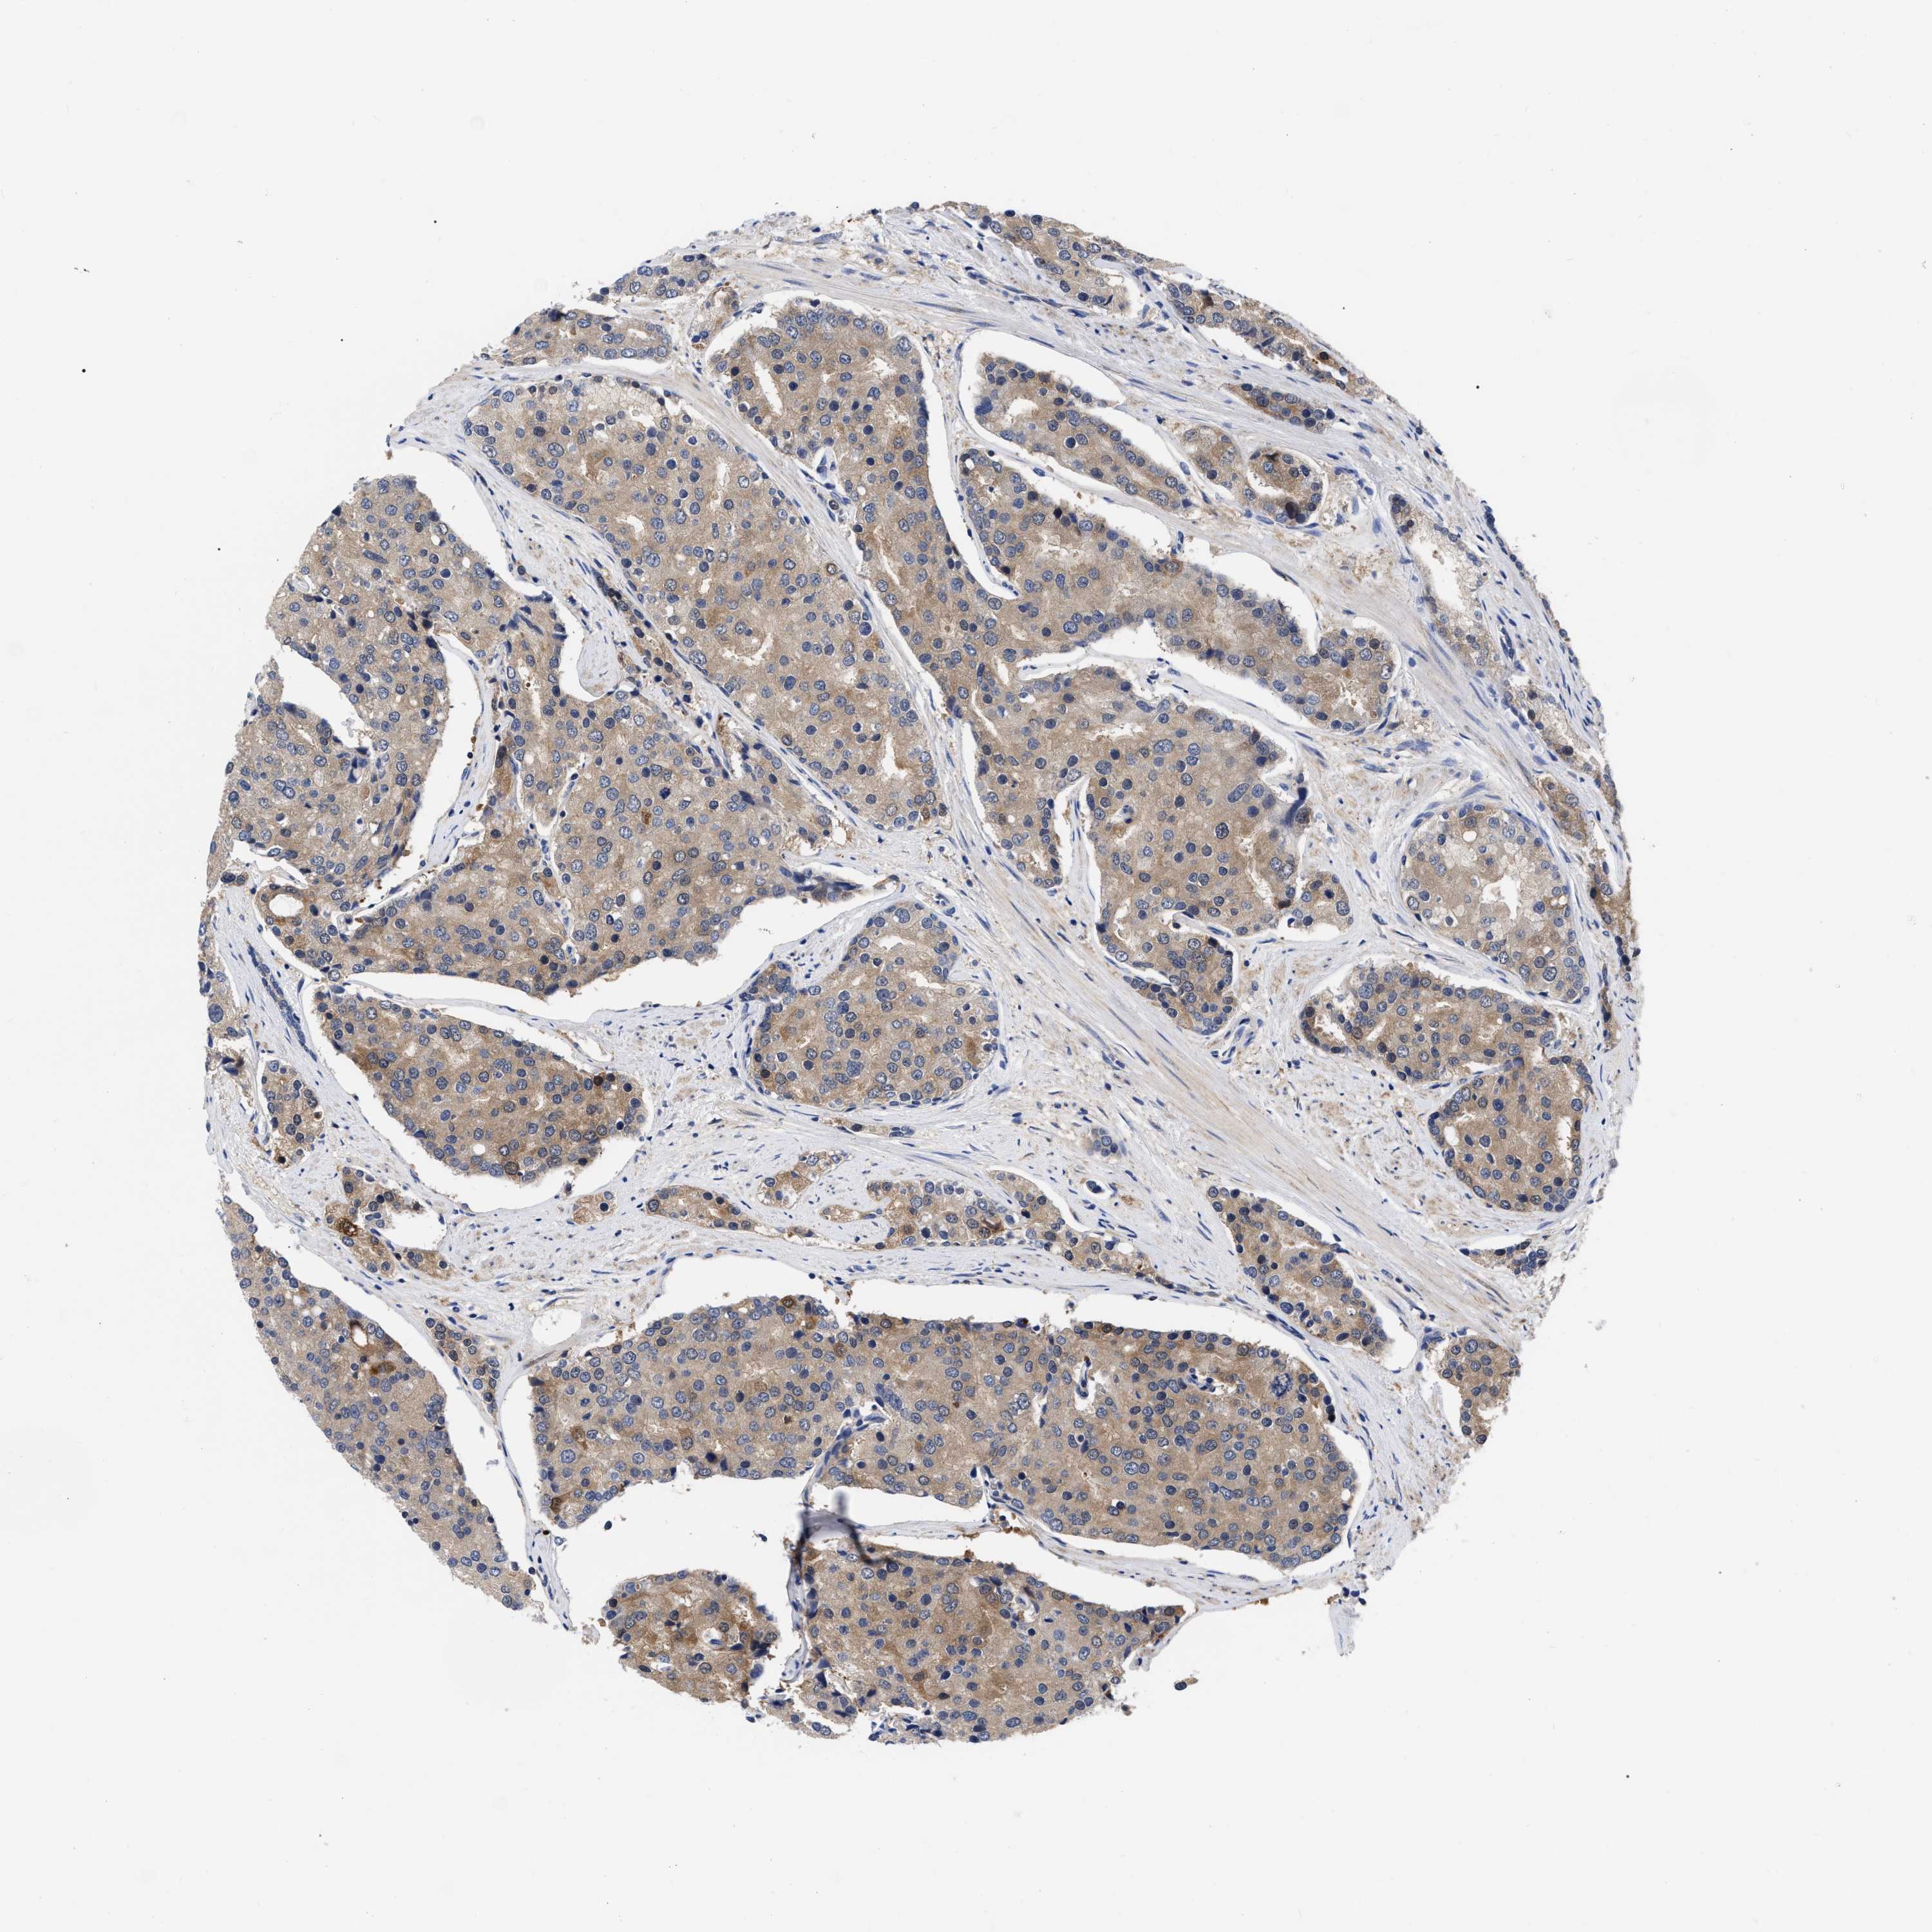

PROSTATE CANCER - Protein expressioni

A mouse-over function shows sample information and annotation data. Click on an image to view it in a full screen mode. Samples can be filtered based on level of antibody staining by selecting one or several of the following categories: high, medium, low and not detected. The assay and annotation is described here.

Note that samples used for immunohistochemistry by the Human Protein Atlas do not correspond to samples in the TCGA dataset.

Antibody stainingi

Antibody staining in the annotated cell types in the current human tissue is reported as not detected, low, medium, or high, based on conventional immunohistochemistry profiling in selected tissues. This score is based on the combination of the staining intensity and fraction of stained cells.

Each image is clickable and will lead to virtual microscopy that enables deeper exploration of all samples and also displays staining intensity scores, fraction scores and subcellular localization as well as patient and tissue information for each sample.

Antibody HPA019725

Antibody HPA028285

Staining

High

Medium

Low

Not detected

Intensity

Strong

Moderate

Weak

Negative

Quantity

>75%

75%-25%

<25%

None

Location

Nuclear

Cytoplasmic/membranous

Cytoplasmic/membranous,nuclear

Adenocarcinoma, High grade

Adenocarcinoma, Low grade

Adenocarcinoma, Medium grade